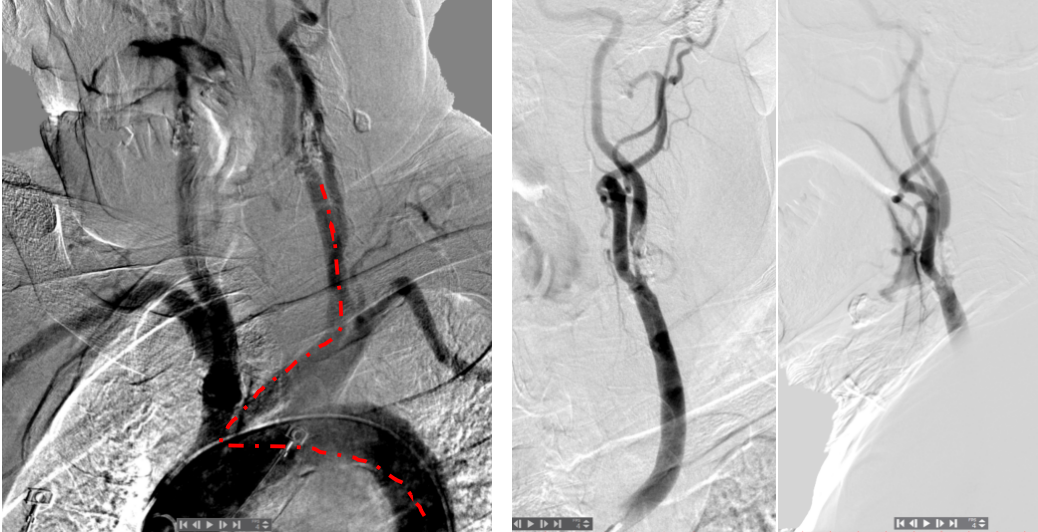

有了稳定的通路,接下来就是常规的上保护伞→预扩→释放支架→后扩,过程顺利。图5分别是保护伞到位、支架释放后、手术结束前的造影。

图5. 保护伞到位、支架释放后、手术结束前造影。

Syed等人(J Endovas Ther, 2011)报道了另外一种利用颞浅动脉的方法:超声引导下穿刺颞浅动脉,置3F鞘,0.014"微导丝经颞浅动脉进入颈总动脉,再经股动脉鞘送出体外。这时候在体外把导丝颞浅动脉的一端用钳子或其他工具牢牢固定住,就可以轻松把导引导管送到颈动脉内了(图7)。

图7. Syed等人2011年报道的技术。

Myrcha等人(J Endovas Ther, 2024)将这种技术做了改进:0.014"微导丝送到主动脉弓后,用抓捕器把微导丝捕获拖入经股动脉置入的导引导管(图8),这就解决了微导丝不一定能顺利超选进入股动脉导管的问题。

图8. Myrcha等人2024年报道的技术。